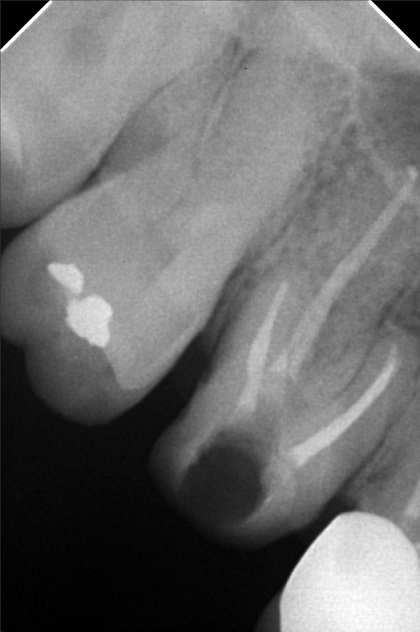

Edit Record Check our patient data records. Add patient information Patient Info Profile picture Last Name First Name Middle Name Birthdate Age Street Barangay City Country Zip Code Contact number Email Procedure 07/26/21- implant placement- 16-8.5mm 15-8.5mm/ 47/46/36/37 with prf/ cgf/ bone fillers 11/13/21 - 15 healing abutment installed- 3mm (6mm) 46/45 healing abutment installed- 6mm req for 3mm 12/17/21 - installation of abutments/ impression 12/22/21- PMMA 46/47/36/37 (12/29) final impression 2/3/22 - 4 implants 4.3x10mm lateral sinus lift LEFT 05/07/22- OP with ozone PA xray 05/13/22 recementation 22 veneers 05/31/22- Redo 23 Veneers PFZ- Temporary ***for healing abutment implants 08/12/22- installation of healing abutments 9/6/22- scan body/ intra oral scanned ***request for alginate impression *** shade A3 cervical A2 body 10/07/22- installed 4 units 24/25- with pink porcelain crown 26/27 ameloplasty mesial of 28 abutment sealed with TF Zirconia crown- screw retained 12/17/22- OP 05/13/23- xray/ozone 09/23/23- OP/AIRPOLISHER XRAY 10/13/23 -RCT #41 - flexion root opening - dressing formocresol 10-27-23- RCT #41 18.5 mm Champenol Flexion root 11-03-23- Obturation #41 MTA Fillapex, Master wire = fine 11/10/23 # 43 - veneer; emax # 42 - veneer; emax # 41 - crown; PF Z # 31 - veneer; emax # 32 - veneer; emax shade A3/ B2 11/17/23- Installation of Veneers- 43,42,31,32 (emax) Crown Zirconia- 41 Cement: choice 2 Prosapac Vacummed sheet retainer 05/25/24 OP w/ air polisher 03/29/25 OP w/ air polisher LC #42 (I) cementation repair veneer 06/13/25 Upper #23-PFZ Lower # 32,33- Zirconia bal.70k 06/18/25 installed PFZ crown #23 zirconia crown #33,#32 bal,. paid 08/08/25 Dx:peri implantitis #44/15 moldable bone-HUBT .m30 w/PRF #44 implant moldable bone HUBT .m30 w/ PRF #15 scaling and planning disinfect w/ citric acid irrigate w/ citric acid Rx: Celecoxib 400mg Tranexamic 500mg Co amoxiclav 625mg, Orahex Prednisone 10mg for 10 days 02/24/26 LC on iplant #25-Occ #23- Recement veneer 02/25/26 Repair 04/01/26 #13 DCV File 01cb0af9-a7ec-487f-a76f-2b7aa0463be3.jpeg File 2 9941df4f-eadd-49c9-a9ad-b0f3e6f2052a.jpeg File 3 2d4f20db-c762-4f0e-9fe3-4a3ecc7b62c0.jpeg File 4 a55f6852-691c-4c51-ad5c-f6f58a1f269c.jpeg File 5 a965f478-086f-4edc-bdde-4c4f9bcd41ff.jpeg File 6 d31d3680-98bc-43a6-bcb1-c3d0d4b8c1c5.jpeg File 7 roleenxray.jpg File 8 roleen_del_prado.jpg File 9 rollen_del_prado_02.jpg File 10 rpleen_del_prado_04.jpg File 11 1000005163.jpg File 12 File 13 File 14 File 15 File 16 File 17 File 18 File 19 File 20 Retain Record Retain Record Yes No Save Your Changes